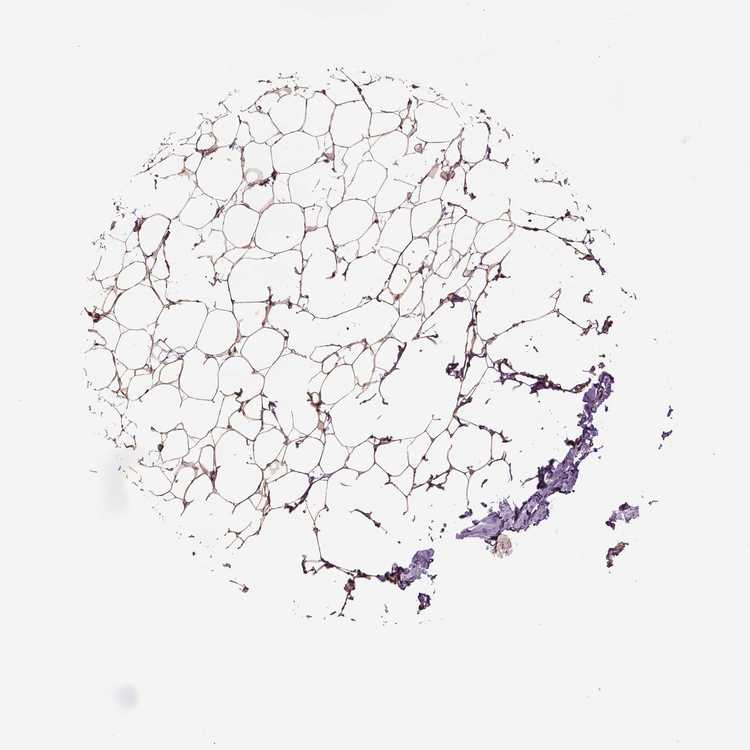

BREAST - Antibody stainingi

Antibody staining in the annotated cell types in the current human tissue is reported as not detected, low, medium, or high, based on conventional immunohistochemistry profiling in selected tissues. This score is based on the combination of the staining intensity and fraction of stained cells.

Each image is clickable and will lead to virtual microscopy that enables deeper exploration of all samples and also displays staining intensity scores, fraction scores and subcellular localization as well as patient and tissue information for each sample.

Antibody HPA069116Antibody CAB005429Antibody CAB039240Antibody CAB069907

Adipocytes HighMediumNot detectedMedium

Glandular cells HighHighMedium-